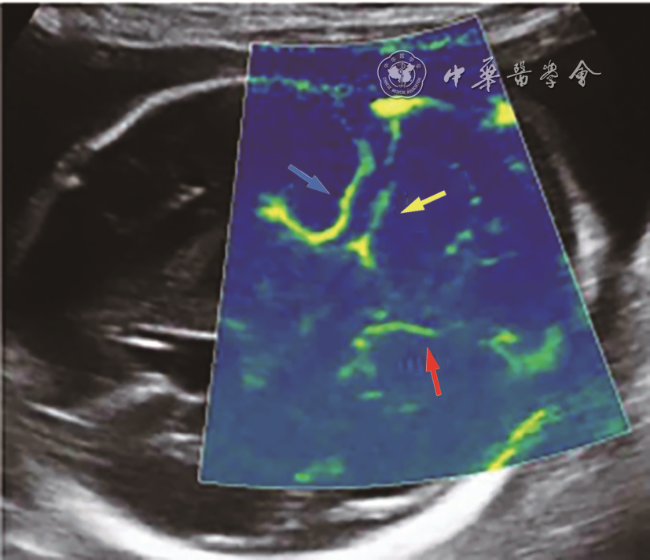

2. 微血流显像检查2例,发育不全侧小脑上动脉均不显示,对侧小脑上动脉可显示(图45)。

图5 孕25周胎儿(例5)产前小脑横切面Micro F显微血流技术图,显示右侧大脑后动脉(蓝箭头所示)及右侧小脑上动脉(黄箭头所示)走行,但左侧仅显示左侧大脑后动脉(红箭头所示),左侧小脑上动脉血流不显示